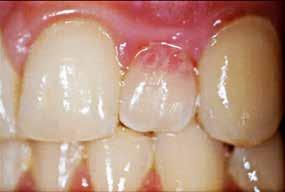

med stor cervikal restaurering facialt (pil) og fistel i den faciale slimhinde ud for første præmolar. B. Røntgenoptagelse viser restaurering i den koronale del (pil) og periapikal læsion under anden præmolar.

Fig. 9. A. Clinical photo of second premolar with large buccal cervical restoration (arrow) and fistula on buccal mucosa below first premolar. B. Radiograph showing restoration in the coronal part (arrow) and periapical lesion under second premolar.